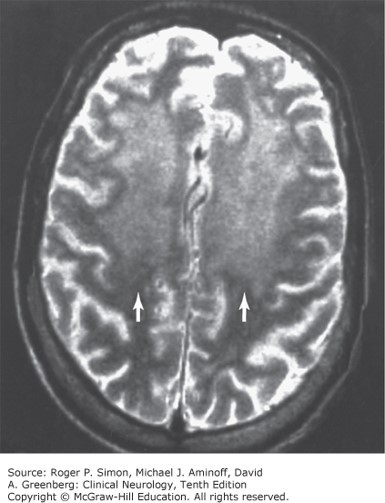

T2-weighted MRI in HIV-associated dementia, showing increased signal intensity (arrows) in subcortical white matter.

Source: Simon RP, Aminoff MJ, Greenberg DA. Clinical Neurology, 10e; 2017.